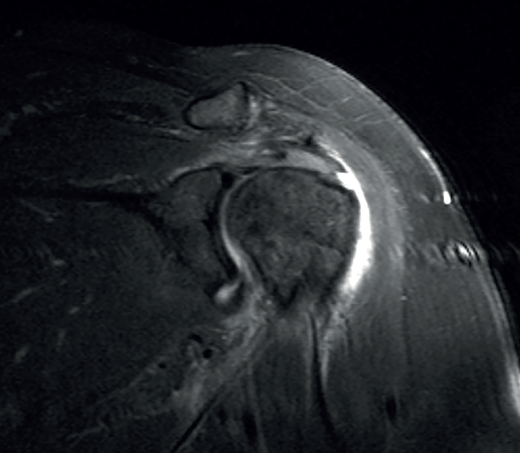

Figure 7. Supraspinatus bursal partial thickness rupture in magnetic resonance imaging scan.

A lesion is classified as being of partial thickness if an abnormal fluid signal intensity in T2 sequencing is seen to extend through a portion of the tendon without affecting its full thickness (Figure 7). These may be bursal or articular lesions, though the latter are more common. There is a possibility that the thickness of the partial lesion may be occupied by scar or granulation tissue, thereby complicating the diagnosis. It has been suggested that the use of arthroMRI in the ABER (abduction + external rotation) position can improve the diagnosis and the typing of these injuries(34). According to Ellman(35), partial thickness lesions can be classified into three grades: grade I (lesion depth < 3 mm), grade II (depth 3-6 mm) and grade III (depth > 6 mm). Taking into account that a healthy supraspinatus measures between 10-12 mm in thickness, grade II lesions affect over 50% of this thickness. Intra-substance lesions are characterized by a fluid-type signal in the thickness of the tendon, without extending to the bursa or joint space.